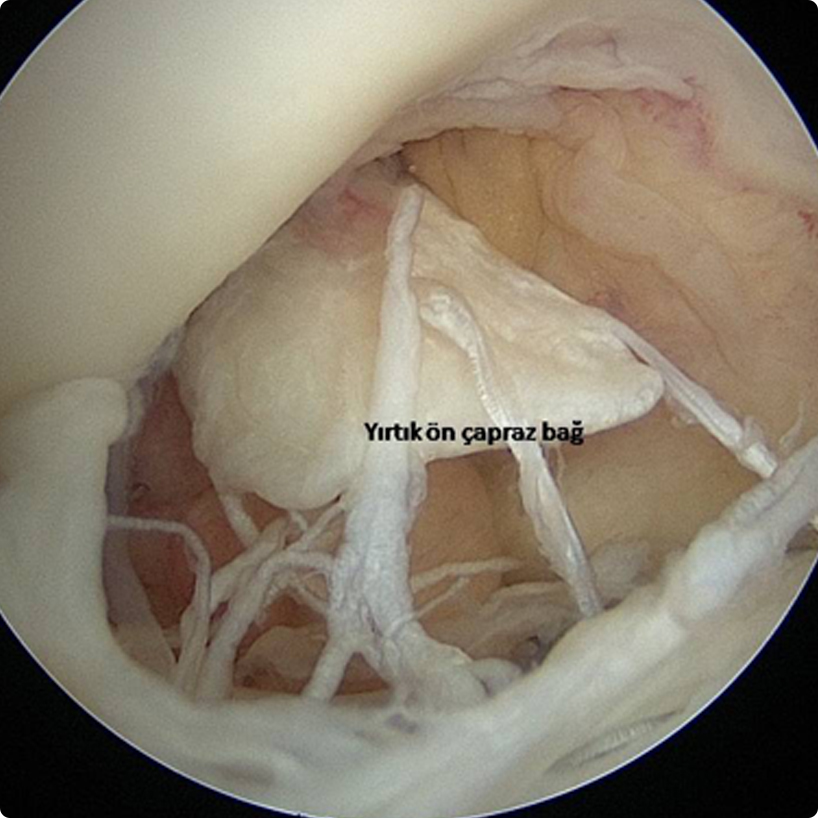

Bağ yırtığı uç uca dikilebilecek bir yırtık şeklinde değildir. sunu1Dolayısıyla cerrahi tedavide bağın yeniden yapılarak onarılması söz konusudur. Bunun için hastanın kendisinden veya kadavra dokularından steril edilerek özel şartlarda alınan bağlar kullanılabilir. Daha çok hastanın kendisinden alınan bağlar kullanılmaktadır.